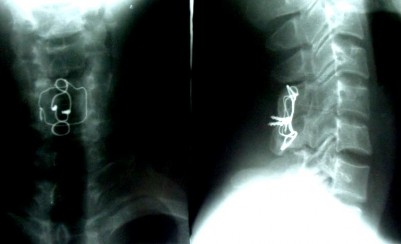

SAU MỔ 3 THÁNG (25-7-2003)

NGHIÊNG (Tái tạo đường cong sinh lý) THẲNG (Chỉ thép vẫn tốt)

SAU MỔ 8 NĂM (4-5-2011)

THẲNG NGHIÊNG

NGỬA CÚI

(Liền xương độ I, chỉ thép tốt, cúi – ngửa không di lệch thứ phát)